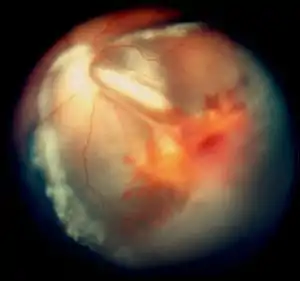

| Vitreous hemorrhage and exudative retinal detachment resembling Coats' disease in a child with cerebroretinal microangiopathy with calcifications and cysts | |

Smaller blood vessels of the retina are abnormally developed and appear tortuous and dilated to a variable extent, typically in one sector and mainly in the peripheral and temporal portions of the retina.[1][2][3][9] This is known as telangiectasia. The vessel walls are weak and leak blood plasma and lipid within and underneath the retina. This leakage can lead to exudative retinal detachment, also known as exudative retinopathy in this context. The detachment typically has a yellowish tint because the fluid under the retina contains lipid. These findings mimic Coats disease.[9] Characteristically, the abnormal vessels are localized and the retinal blood vessels peripheral to the abnormal ones seemingly have failed to develop and are thus not seen.

In some eyes, retinal vessels form small nodules on the surface of the retina, known as angiomas.[1] These can bleed and be attached to the vitreous humour. The attachment can cause traction retinal detachment.